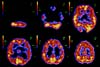

PET che compara l'attività del

cervello normale con quello sotto l'effetto dell'eroina.

Clicca sull'immagine per un ingrandimento. |